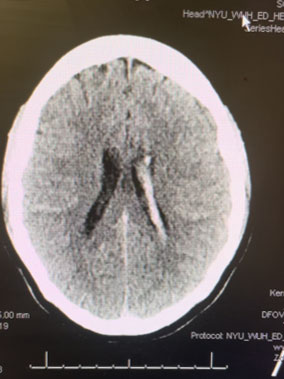

MRI was consistent with a left deep frontal AVM (Figure 2).

Fig. 2